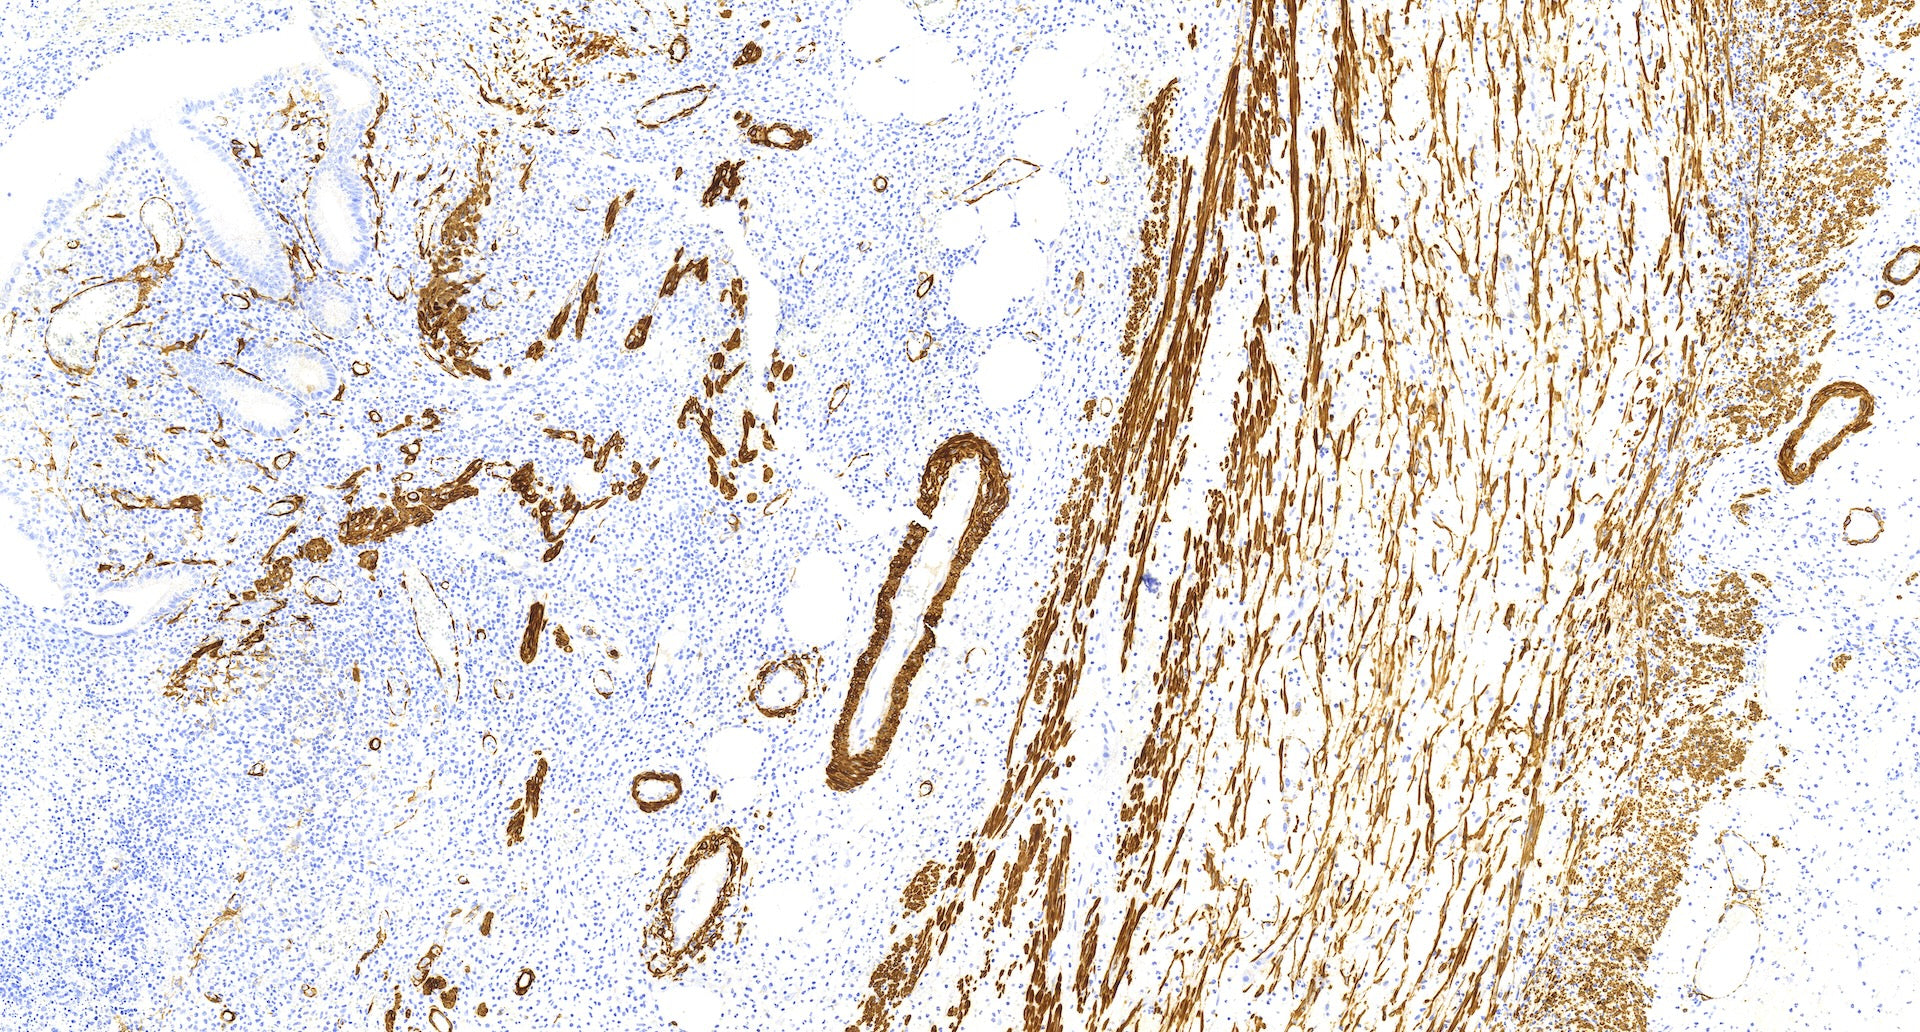

El marcador de actina del músculo liso (SMA) se ha utilizado ampliamente en diversos contextos. Los dos anticuerpos comúnmente utilizados para la detección de AME son el anti-SMA y la actina específica del músculo (clon HHF-35). La AME se conoce como un marcador sensible para la diferenciación mioepitelial. Sin embargo, carece de especificidad ya que cualquier célula con una expresión significativa de actina mostrará una tinción positiva para AME. En el tejido mamario, los miofibroblastos y los vasos sanguíneos suelen tener una tinción positiva para AME. Esto puede plantear desafíos en los casos en los que hay miofibroblastos o vasos sanguíneos muy cerca de la lesión epitelial que se examina, como en la adenosis esclerosante, las cicatrices radiales, las lesiones papilares o el carcinoma ductal in situ (CDIS).

A pesar de su falta de especificidad, la AME sigue siendo un marcador útil debido a su alta sensibilidad. Ayuda a resolver el diagnóstico diferencial en un número importante de casos. Al considerar el patrón de tinción y el contexto, los patólogos pueden interpretar los resultados y diferenciar entre diferentes lesiones.